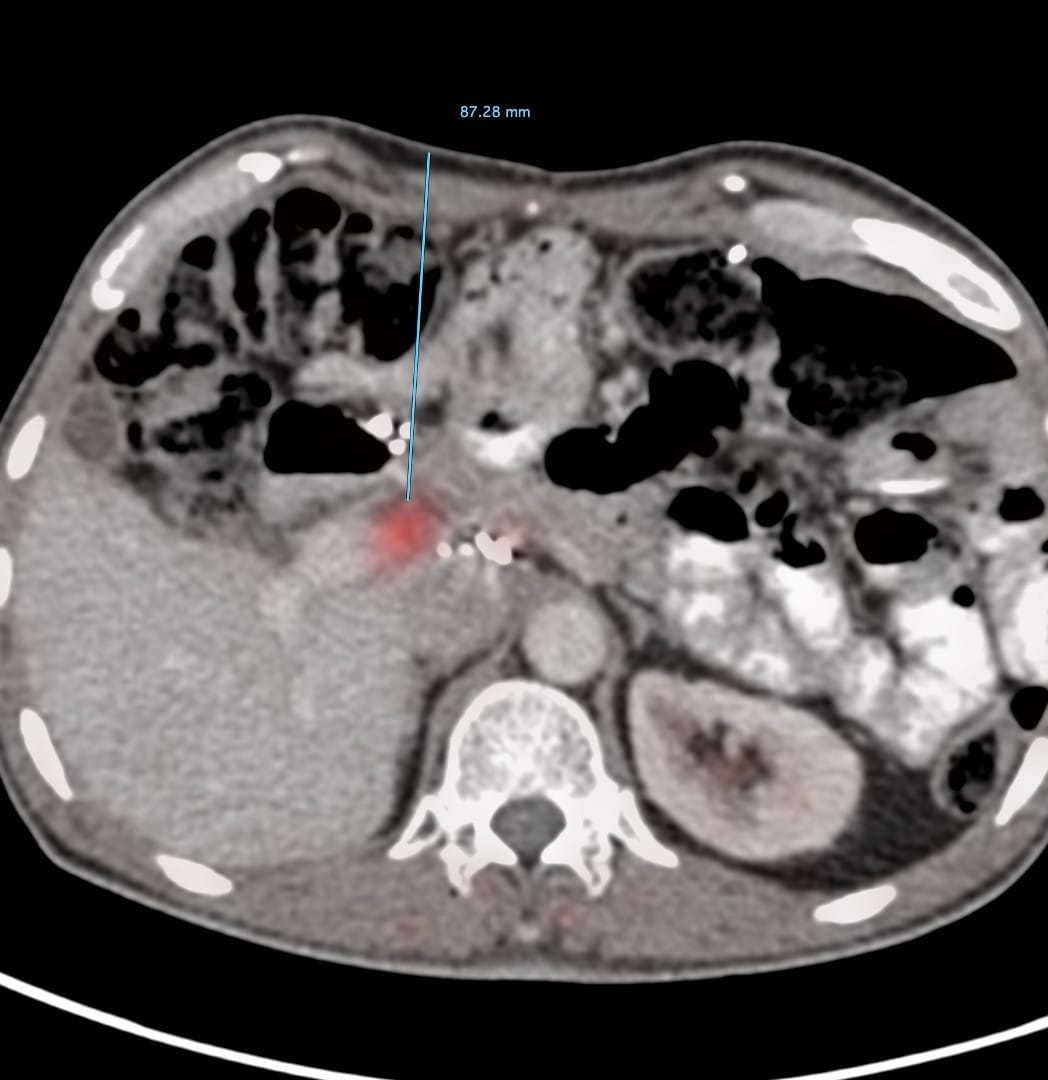

61-years old treated for Ca stomach with a Whipple’s had a new active node on a FAPI PET/CT.

What would be your approach, given the overlying leash of bowel loops and overlying vessels?

The video below describes the case. The biopsy was performed using multiple techniques, including the blunt-tip, the fixed-point methods and intra-procedural intravenous contrast.